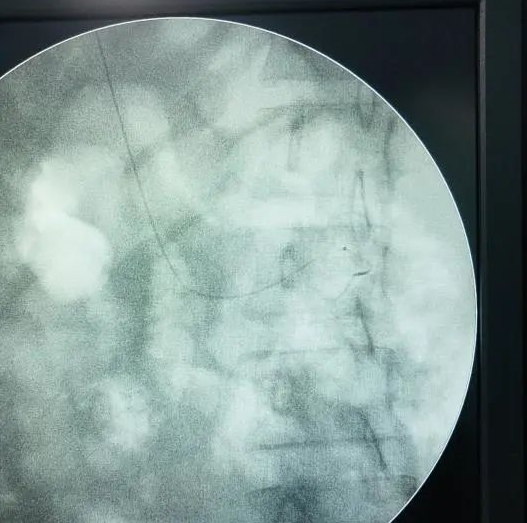

2、在上级医师的指导下重新摆体位在C臂机辅助下尝试拔管,未能拔出,C臂机摄片可见导管折弯,请麻醉科、影像科、骨科、外科、妇产科、医务科等相关科室会诊。

图2 手术室C臂机下的成像